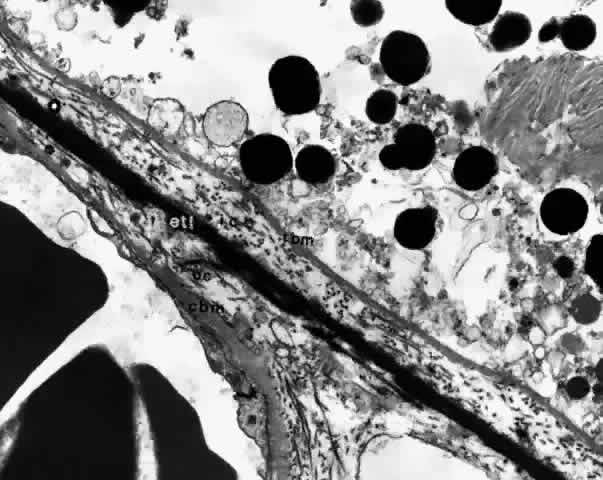

Bruch's membrane, also called the lamina vitrea, is the inner layer of the choroid. This thin, acellular, well-delineated zone between the retina and choroid extends from the optic nerve to the ora serrata. Composed of elements from both the retina and the choroid, Bruch's membrane is an integral part of the choroid. From internal to external, the membrane is formed of five layers: the basement membrane of the RPE, the inner collagenous zone, the elastic tissue layer, the outer collagenous zone, and the basement membrane of the choriocapillaris (Fig. 8).

Fig. 8. Bruch's membrane. Basement membrane of retinal pigment epithelium (rbm), inner collagenous zone (ic), elastic tissue layer (etl), outer collagenous zone (oc) and basement membrane of choriocapillaris (cbm). (× 14,500)

Bruch's membrane is thickest near the optic disc, measuring 2 to 4 μm, and gradually decreases in thickness to 1 to 2 μm peripherally.16 The innermost layer, the basement membrane of the RPE, is a continuous membrane measuring 0.3 μm thick. The outer layer, the basement membrane of the choriocapillaris, is 0.14 μm thick and is discontinuous at the intercapillary septa. The inner and outer collagenous layers are continuous and measure 1.5 μm and 0.14 μm, respectively. The middle elastic tissue layer is discontinuous. Normally, the layers of Bruch's membrane are so closely interwoven that they cannot be separated in a healthy globe.17–20